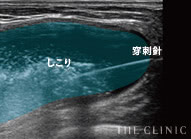

実際のエコー画像

溶解液注入   的確にしこりへ穿刺・注入

吸引・除去後   しこりの消失を確認

目視しながら確実にしこり除去

ヒアルロン酸豊胸のしこりの多くは、注射器による処置で除去することが可能です。ただし、それはエコーでしこりを目視しながら、正確にアプローチできた場合のみ。触診だけを頼りに治療を行うクリニックもあるようですが、海外では「暗闇の手術」と呼ばれ、とても危険視されている行為です。

一方、THE CLINIC では、乳腺用エコー「エラストグラフィ」で目視しながら、的確にしこりを除去します。最短ルートでしこりを除去するため、体への負担を最小限に抑えることも可能です。